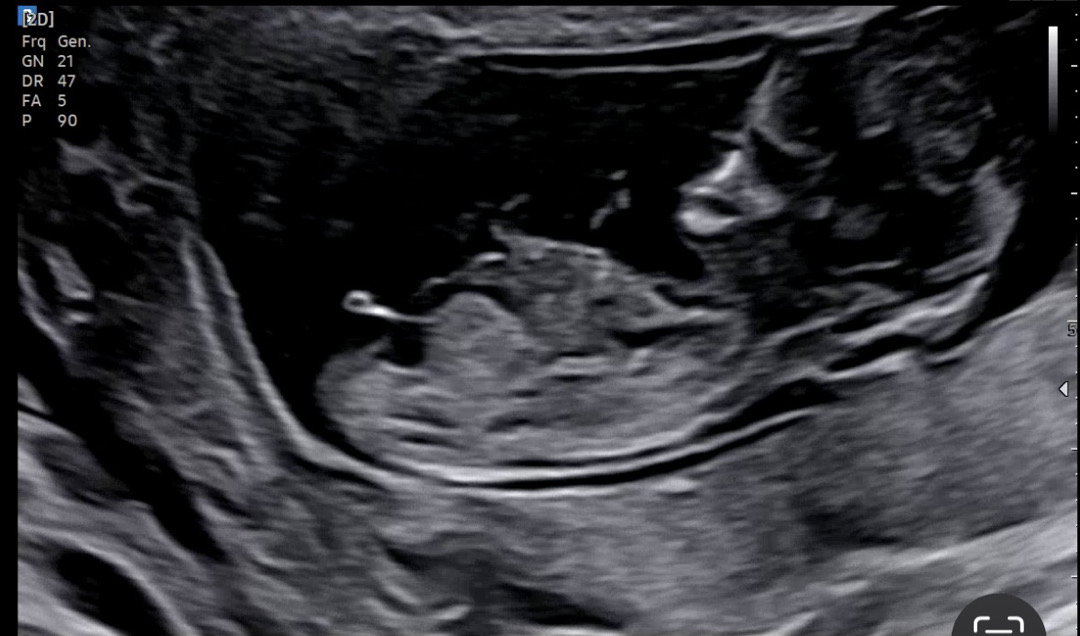

아들 딸 상관없어서 별로 안궁금했는데 11주 6일차에 기형아 검사 받으면서 넘 궁금하네요! 각도법으로 의견 여쭙고 싶습니다~

아들